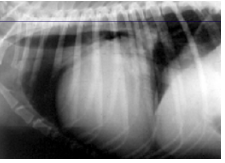

Hemopericardium